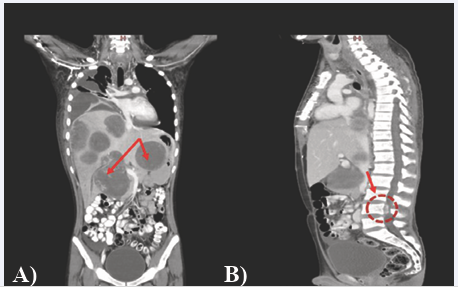

Figure 2 CT Scan chest, abdomen, pelvis with contrast a) coronal view: multiple hypodense lesions with specks of calcification in both lobes of liver (indicated by red arrow), b) sagittal view: the largest epidural component (2.3x1.1cm) along the L4 vertebra.